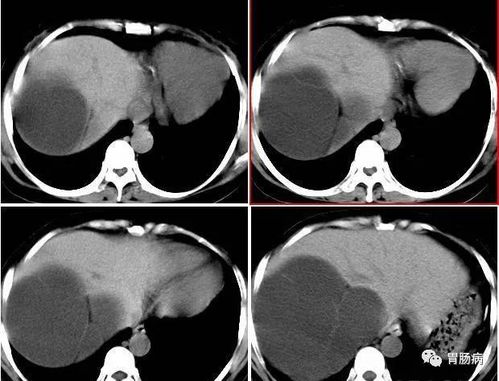

当我们谈论到实际应用时,需要理性看待这些成分的功效。要知道,要从大量洋葱中提取这些抗癌成分,日常食用量很难达到实验浓度。而且,这些物质并非洋葱所独有,其他食物中也同样存在。尽管有欧洲流行病学杂志的研究显示,每天摄入5-6颗洋葱可能降低33%的肝癌风险,但样本量和具体作用机制仍需进一步验证。